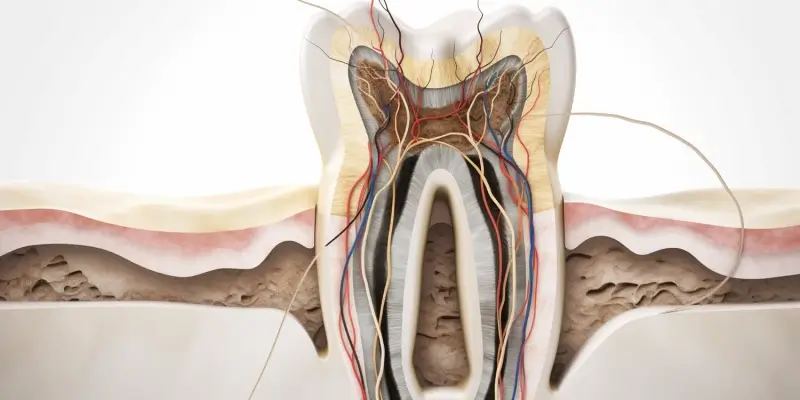

Najlepsze gabinety endodontyczne w Szczecinie oferują szeroki zakres usług, które są dostosowane do indywidualnych potrzeb pacjentów. Podstawowym zabiegiem wykonywanym przez endodontów jest leczenie kanałowe, które ma na celu uratowanie zęba przed ekstrakcją. Specjaliści zajmują się również diagnostyką chorób miazgi zębowej oraz przeprowadzają zabiegi rewizji kanałów korzeniowych w przypadku wcześniejszych niepowodzeń leczenia. Wiele gabinetów oferuje także usługi związane z regeneracją tkanek okołowierzchołkowych oraz leczeniem stanów zapalnych. Nowoczesne technologie, takie jak mikroskopy endodontyczne czy systemy do cyfrowego obrazowania, pozwalają na dokładniejszą diagnozę oraz skuteczniejsze leczenie. Ponadto niektóre gabinety proponują dodatkowe usługi, takie jak konsultacje dotyczące profilaktyki chorób zębów i dziąseł czy porady dotyczące higieny jamy ustnej.

Nowoczesna endodoncja w Szczecinie korzysta z zaawansowanych technologii, które znacząco poprawiają jakość leczenia oraz komfort pacjentów. Jednym z najważniejszych narzędzi jest mikroskop endodontyczny, który pozwala lekarzowi na dokładne zobaczenie struktury kanałów korzeniowych oraz wszelkich anomalii, które mogą występować w ich budowie. Dzięki temu możliwe jest precyzyjne oczyszczenie i wypełnienie kanałów, co zwiększa szansę na powodzenie leczenia. Kolejną innowacją są systemy do cyfrowego obrazowania, takie jak radiografia cyfrowa, która umożliwia uzyskanie wyraźnych zdjęć rentgenowskich przy znacznie mniejszej dawce promieniowania niż tradycyjne metody. To nie tylko zwiększa bezpieczeństwo pacjentów, ale także pozwala na szybsze postawienie diagnozy. Warto również wspomnieć o technologiach laserowych, które są coraz częściej wykorzystywane w endodoncji. Lasery mogą być stosowane do dezynfekcji kanałów korzeniowych oraz usuwania tkanki zapalnej, co przyspiesza proces gojenia i zmniejsza dyskomfort po zabiegu.